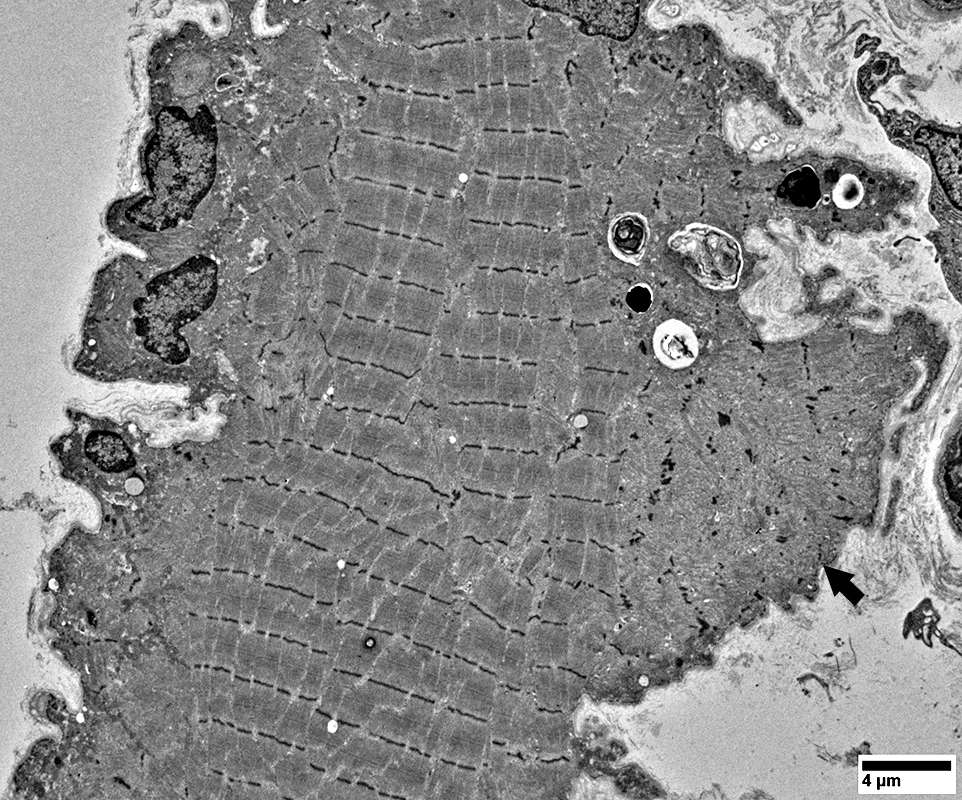

SLONM Rods: Ultrastructure

Rods

Multiple small rods are present in small muscle fibers

May be extensions from Z-bands (Arrow)

Often have fibrillar extensions that are not as common in

hereditary rod myopathies

From: R Schmidt